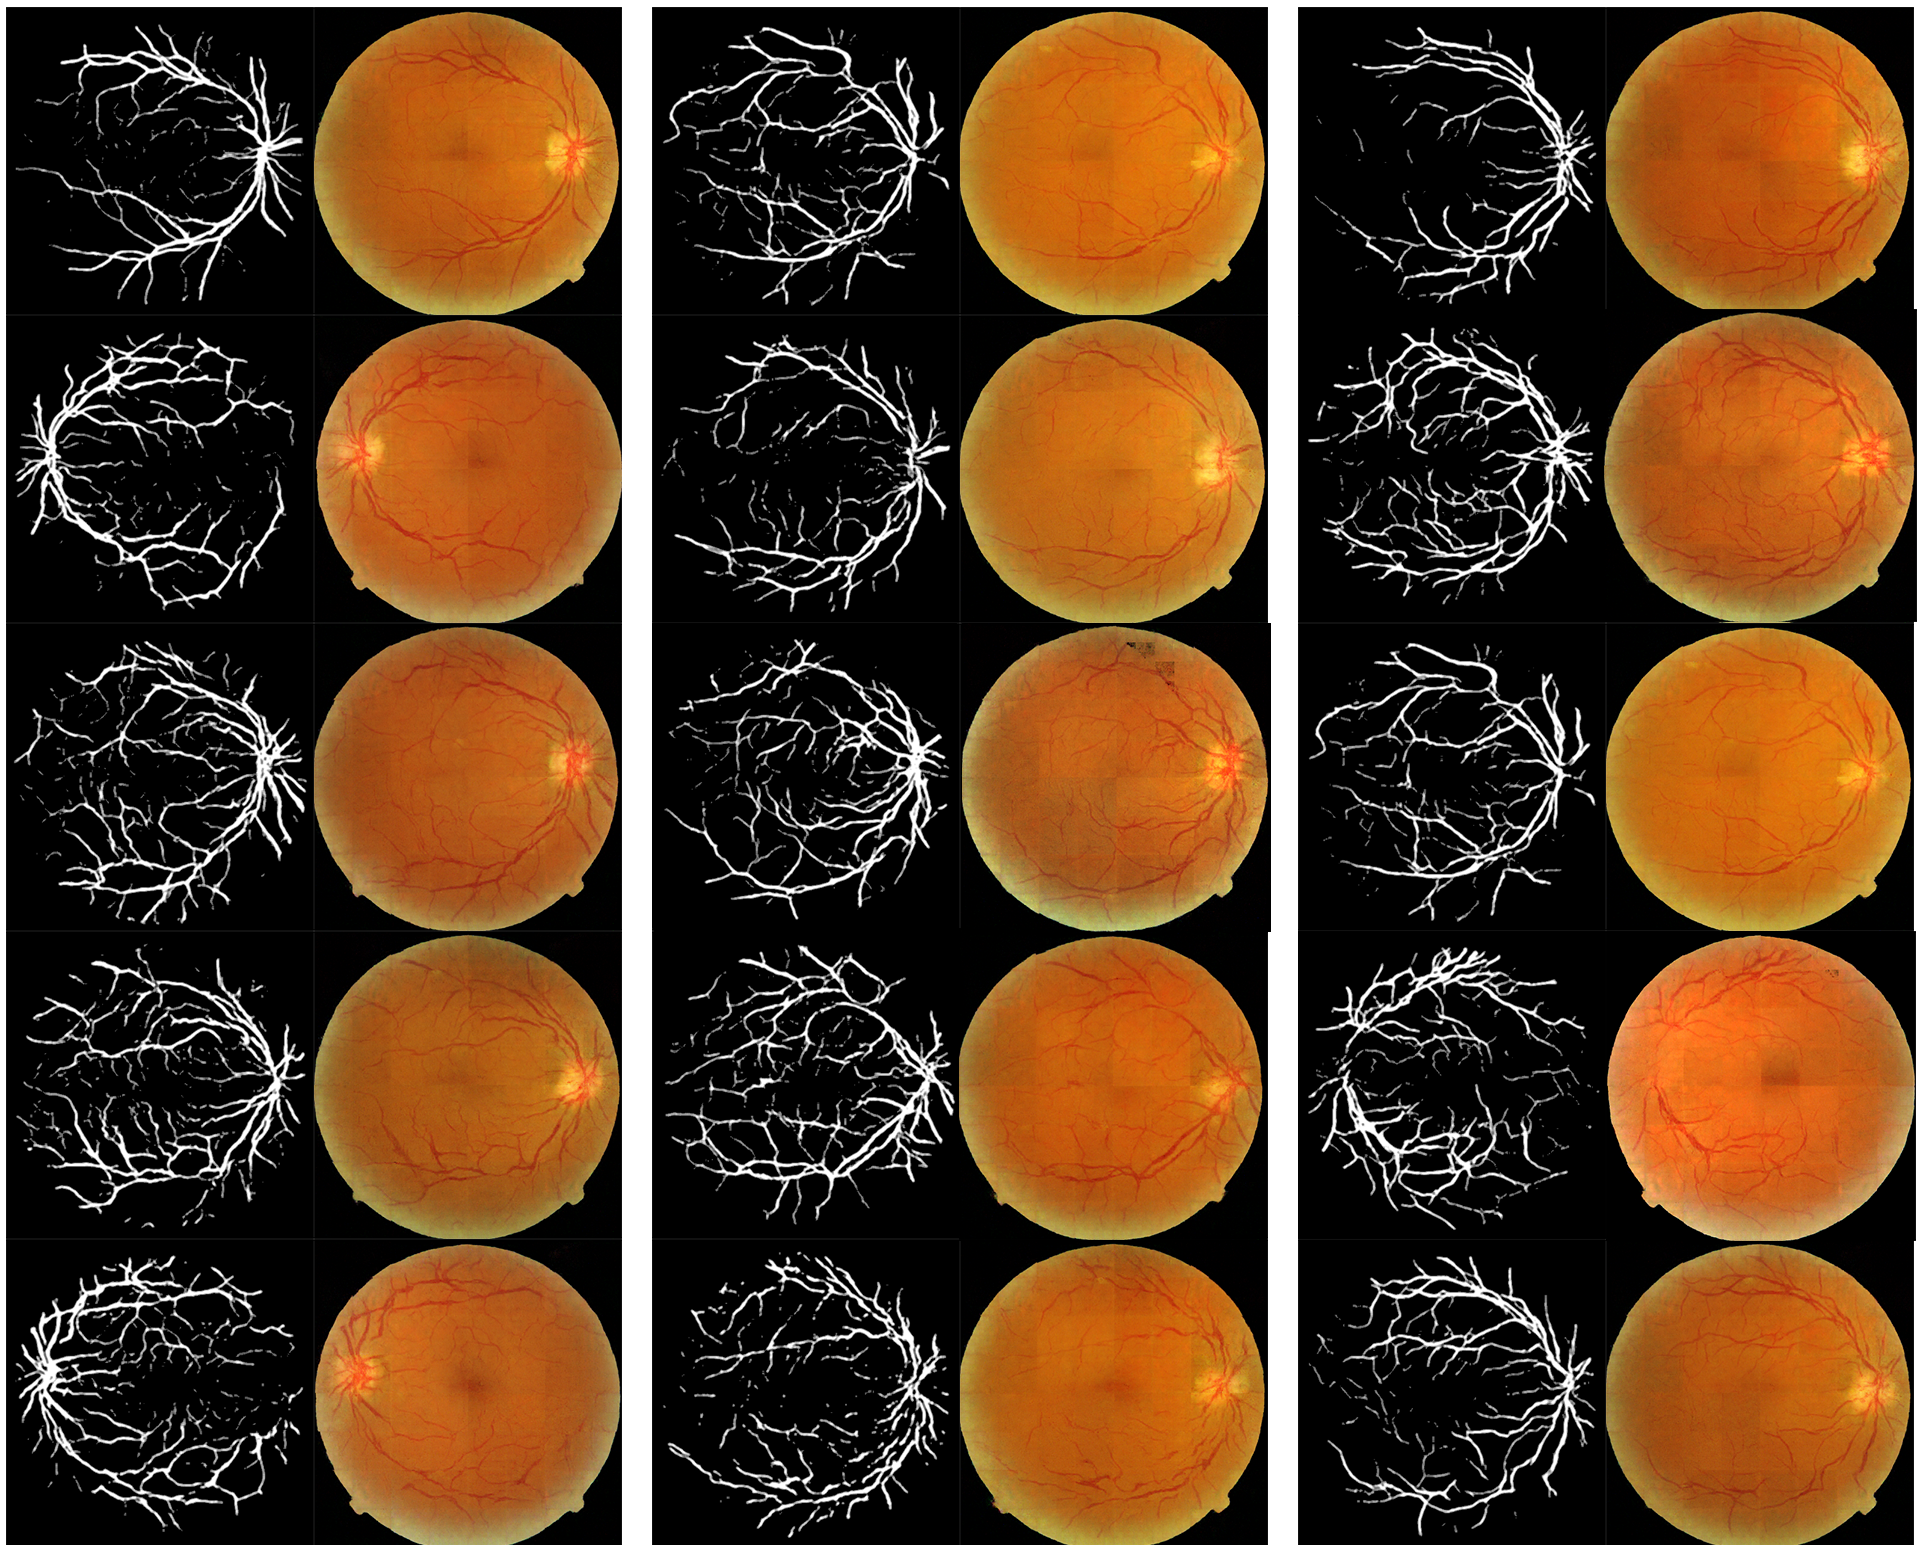

Refer to caption

Figure 5: Examples from the DRIVE dataset and our synthesized dataset.

In addition, the nature of our pipeline produces a wider variety of images than the original dataset. This is because our pipeline generates images that are between the data that formed the distribution. As shown by Figure 5 and Figure 6, our synthetic dataset keeps the general statistical distribution of the real dataset while producing original images. Our pipeline can produce larger quantities of images for effective use in data-driven machine learning tasks, while avoiding legal concerns regarding patient privacy.